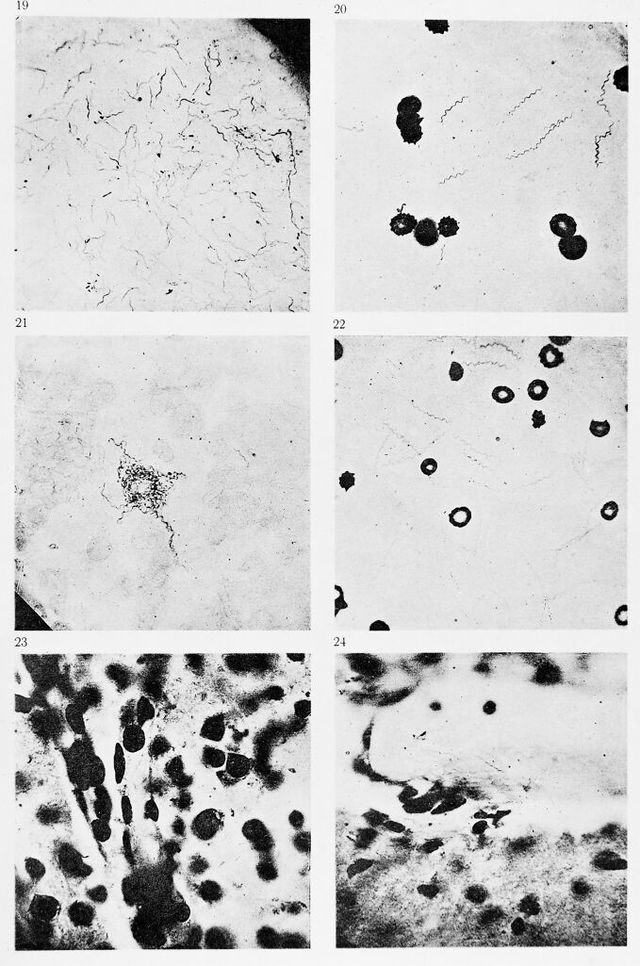

M0013309: Magnifications of various bacilli

Credit: M0013309: Magnifications of various bacilli. Source: Wellcome Collection.